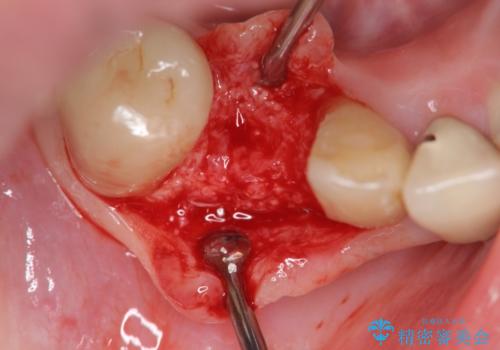

抜歯後、インプラントによる審美・機能改善を希望されたのでインプラント埋入に先立ち吸収した骨の再生を計画します。

歯を失う原因が虫歯や根尖病変などはなく、歯周病や歯の破折等周囲の骨を吸収する原因の場合はインプラント治療を行うに先立ち骨の造成が必要なことがあります。